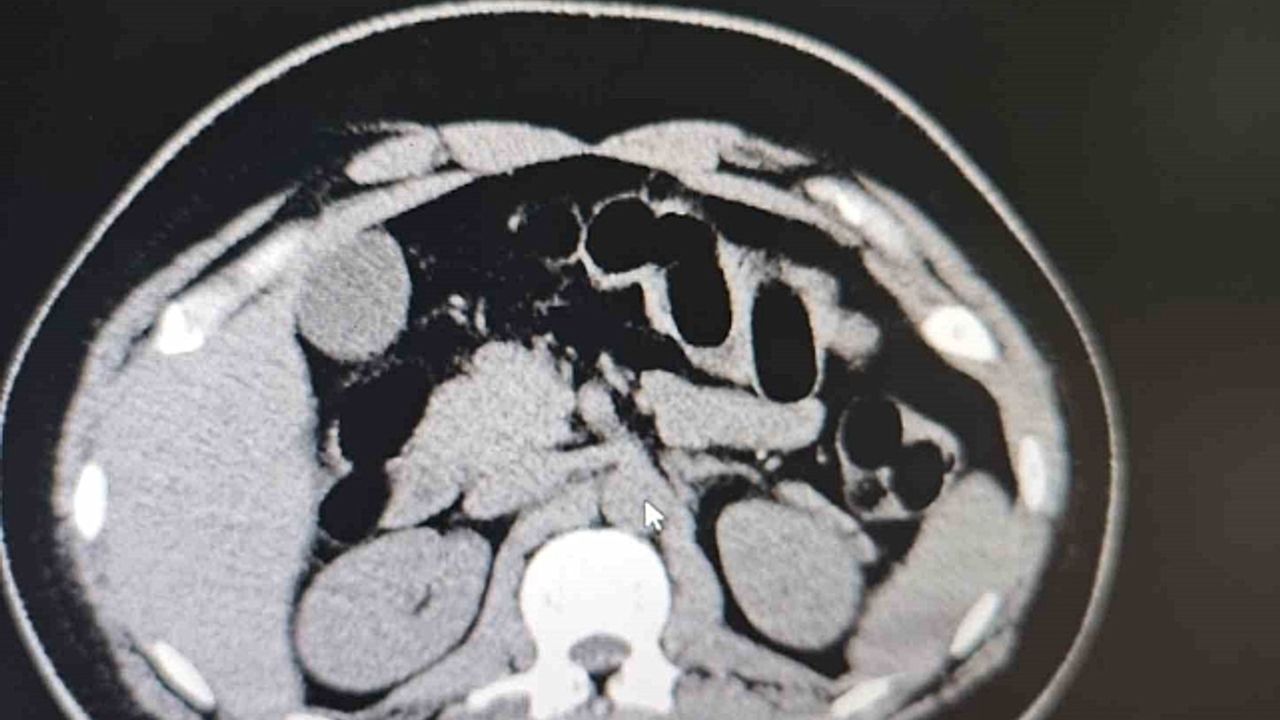

Muş Valiliğinden yapılan yazılı açıklamada, 'Muş İl Emniyet Müdürlüğü Narkotik Suçlarla Mücadele Şube Müdürlüğümüz ekiplerince, ilimiz ve Batı illerine yönelik uyuşturucu madde sevkiyatının önlenmesine yönelik yürütülen risk analizi çalışmaları sonucunda, bir şüphelinin uyuşturucu madde taşıdığı değerlendirilmiştir. 25 Aralık 2024 tarihinde saat 02.20'de, şüphelinin bulunduğu şehirlerarası yolcu otobüsü, ekiplerimizce il merkezine girişte oluşturulan kontrol noktasında durdurulmuştur. Otobüste yolcu olarak bulunan S.S. isimli şahıs, görevlilerimizin sorgulaması sonucunda şüpheli görülerek hastaneye sevk edilmiştir. Hastanede yapılan iç beden muayenesi ve tomografi görüntüleri sonucunda, şahsın midesinde uyuşturucu madde taşıdığı tespit edilmiştir. Hastanede yapılan tespit sonrasında şüpheli şahsın midesinden toplam 84 adet kapsül içerisinde daralı ağırlıkları 842 gr gelen eroin maddesi ele geçirilmiştir. Şüpheli şahıs, 'Uyuşturucu ve Uyarıcı Madde Ticareti' suçundan gözaltına alınmış, işlemlerinin ardından adli makamlara sevk edilmiş ve tutuklanmıştır. Uyuşturucu ile mücadelemiz kararlılıkla devam etmektedir' denildi.